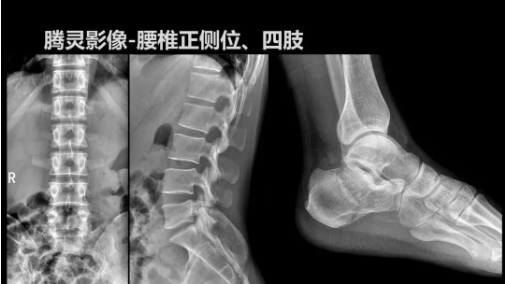

2019年10月19日,82屆秋季CMEF于青島世博城國際展覽中心如期舉辦,國內動態(tài)DR領域的佼佼者安健科技攜新品——“騰靈”多功能診斷專用動態(tài)DR亮相展會現(xiàn)場。

“騰靈”是安健科技的第四代動態(tài)DR產品,可實現(xiàn)全科室應用。如各類常規(guī)的X線檢查、消化道檢查、骨科檢查、婦科、兒科檢查等。此外,安健科技為“騰靈”在真正意義上實現(xiàn)多科室、多功能診斷進行了多項針對性設計。

相較前代產品,“騰靈”在圖像質量方面得到了全面升級,“騰靈”采用17*17非晶硅平板探測器設計,采集矩陣達3072*3072,動態(tài)范圍達16bit,為成像提供超大視野的同時保證成像質量,此外,該款機型可根據醫(yī)療機構的差異化需求而選配不同的動態(tài)平板探測器,以此來適應不同階層用戶所需。